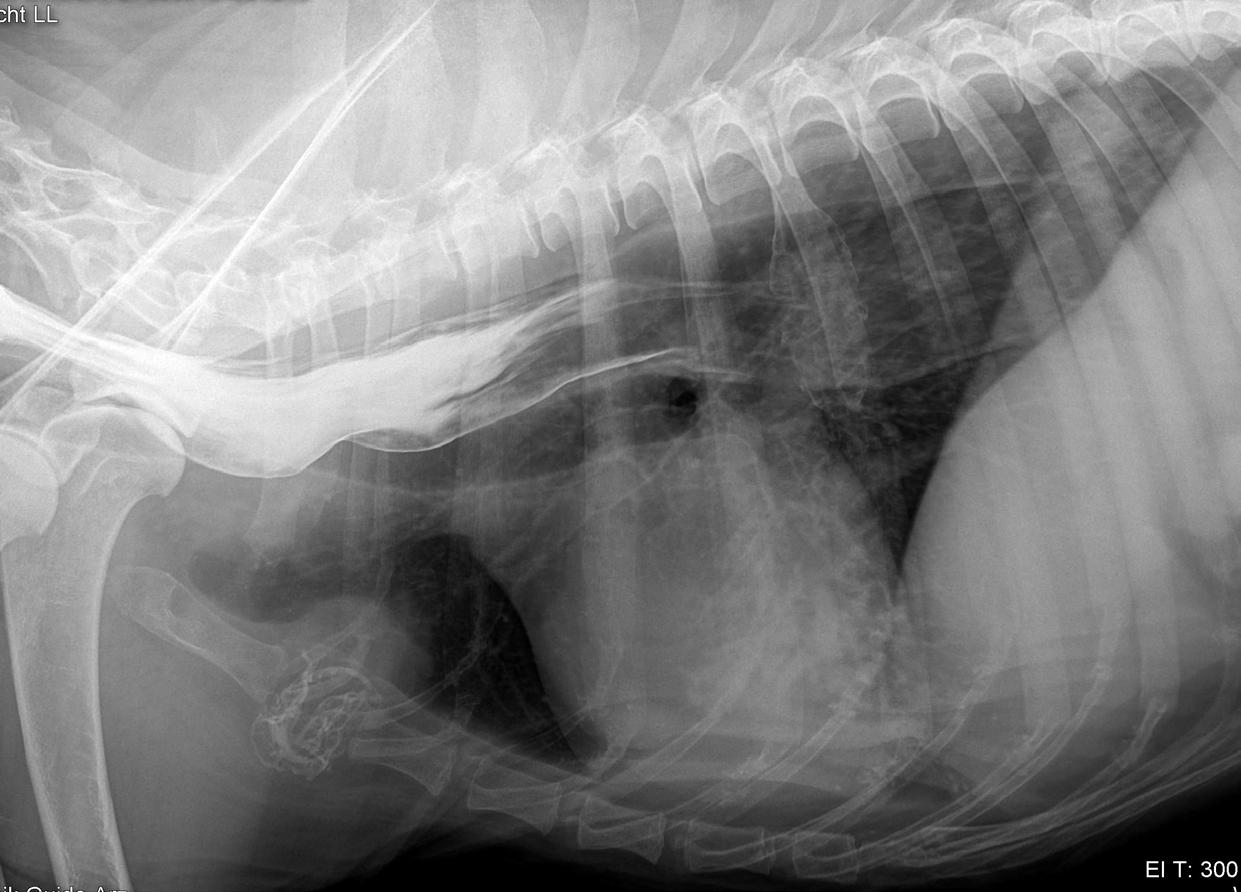

“Megaesophagus in dogs is a condition characterized by a dilation or enlargement of the esophagus, which is the muscular tube that carries food from the mouth to the stomach. This dilation is often due to weakness or dysfunction of the muscles in the esophageal wall, making it difficult for food and liquid to pass into the stomach properly.”

Megaesophagus refers to either focal or widespread muscle weakness of the esophagus; it is categorized into congenital or acquired weakness. In the practice of small animals, this condition is mostly encountered in dogs, though it is occasionally seen in cats. The breeds most prone to this condition include Miniature Schnauzer, Great Dane, Dalmatian, Chinese Shar-Pei, Irish Setter, German Shepherd, Golden Retriever, Labrador Retriever and Collies. Rhodesian Ridgebacks are not a predisposed breed.

In a veterinary clinic, while conducting a clinical examination of a dog, one might observe additional signs such as heightened respiratory

sounds, muscle wasting, and particular attention should be given to assessing cranial nerve reflexes. The diagnosis is most easily made using radiographic imaging, sometimes concurrently with contrast imaging, which, by staining the pathways, reveals expansions. In brachycephalic breeds, smaller, more tortuous placements of the esophagus are normal and should not be confused with megaesophagus.

Dog with Megaesophagus. Photo by Susanne Neu

DIAGNOSIS OF MEGAPHAGUS

One day our 12-year-old Rhodesian Ridgeback female began to cough, with food coughing up again and again. Since there was no improvement in sight, we consulted our veterinarian. After my description of the problem and a subsequent X-ray with contrast medium, the diagnosis was made quickly. Hanna has pneumonia caused by a Megaphagus.